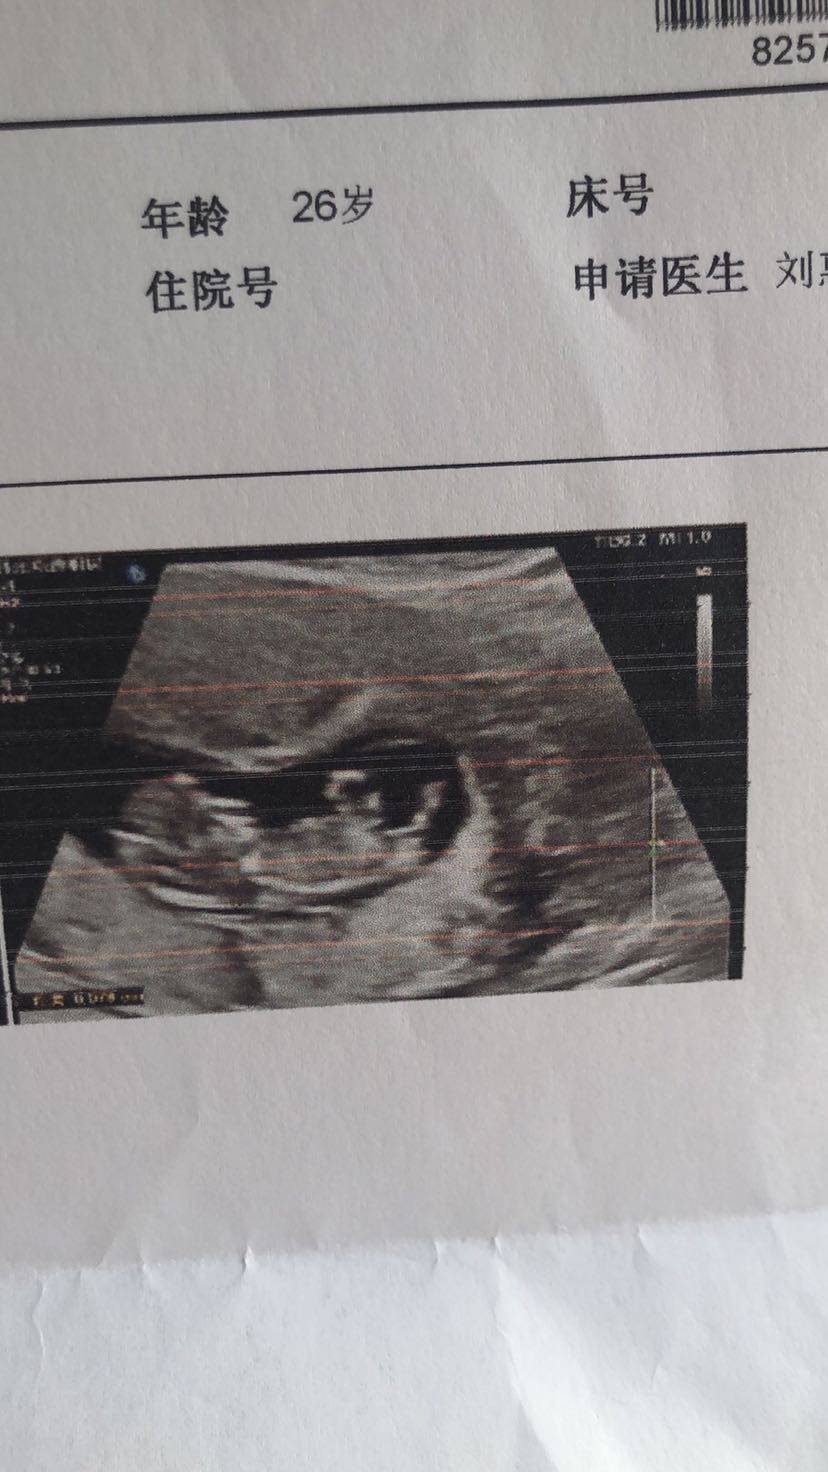

前几天12周的时候去做了nt,没想到不太顺利,宝宝👶比实际孕周小两周,太小做不了nt,b超的大夫也是很负责的扒拉了我半个小时,最后也是没办法,还是太小看不清。拿着单子去找大夫,我说是不是因为我吐了一个月他才小两周啊,大夫说不是,跟这没有关系,跟你的末次月经不符合而已,我们重新算一下。算完之后预产期到9.10号,两周之后再来复查nt。最近碰到的大夫都不错。附上小家伙第一张照片。还有他可爱又磨人的姐姐🧍♀️